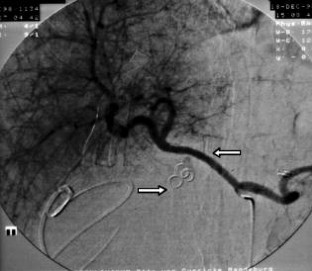

Wir berichten über das diagnostische und therapeutische Vorgehen anhand von 7 Patienten mit Blutungen aus der A. gastroduodenalis (n=5) nach pankreaschirurgischen Interventionen bei Pankreaskopfkarzinom, Rezidiv eines Liposarkoms und chronischer Pankreatitis, der A. hepatica communis (n=1) bei chronischer Pankreatitis und der A. mesenterica superior (n=1) nach akuter Pankreatitis. Anhand von 4 Kasuistiken werden unsere Erfahrungen mit der Implantation von Stentgrafts (Hemobahn®-Prothesen) vermittelt. Den Vorteil der Stentgrafts sehen wir in der sofortigen Blutstillung bei fehlendem Kontakt der Endoprothese zu infiziertem Gewebe und Erhalt der Perfusion des abhängigen Organs. Unsere positiven Erfahrungen mit diesen interventionellen Therapieverfahren erfordern jedoch weitere klinische Untersuchungen, wobei im Mittelpunkt die Indikationen, die technische Erfolgsrate, die stentbedingten Komplikationen und die Langzeitverläufe stehen sollten.

Spontaneous or postoperative hemorrhage into the abdominal cavity due to inflammatory vessel arrosion represents an uncommon but menacing situation. According to the literature, such hemorrhage is associated with a lethality of nearly 2%. Therapeutical options include reoperation and interventional radiological techniques such as endovascular catheter techniques with stent graft implantation or the embolization of vessels. We report on the management of seven cases with hemorrhage either from the gastroduodenal artery (n=5) following pancreatic surgery for pancreatic carcinoma, liposarcoma, and chronic pancreatitis or from the common hepatic artery (n=1) and the superior mesenteric artery (n=1) following chronic pancreatitis. The present article describes our experiences with stent graft implantation (hemobahn prosthesis) in four cases. Based on these experiences, we see the advantages of stent grafts in primary hemostasis without any contact to infected tissue and the preservation of regular perfusion. However, further clinical data are required focussing on indication, technical success rates, stent-related complications, and long-term outcome.